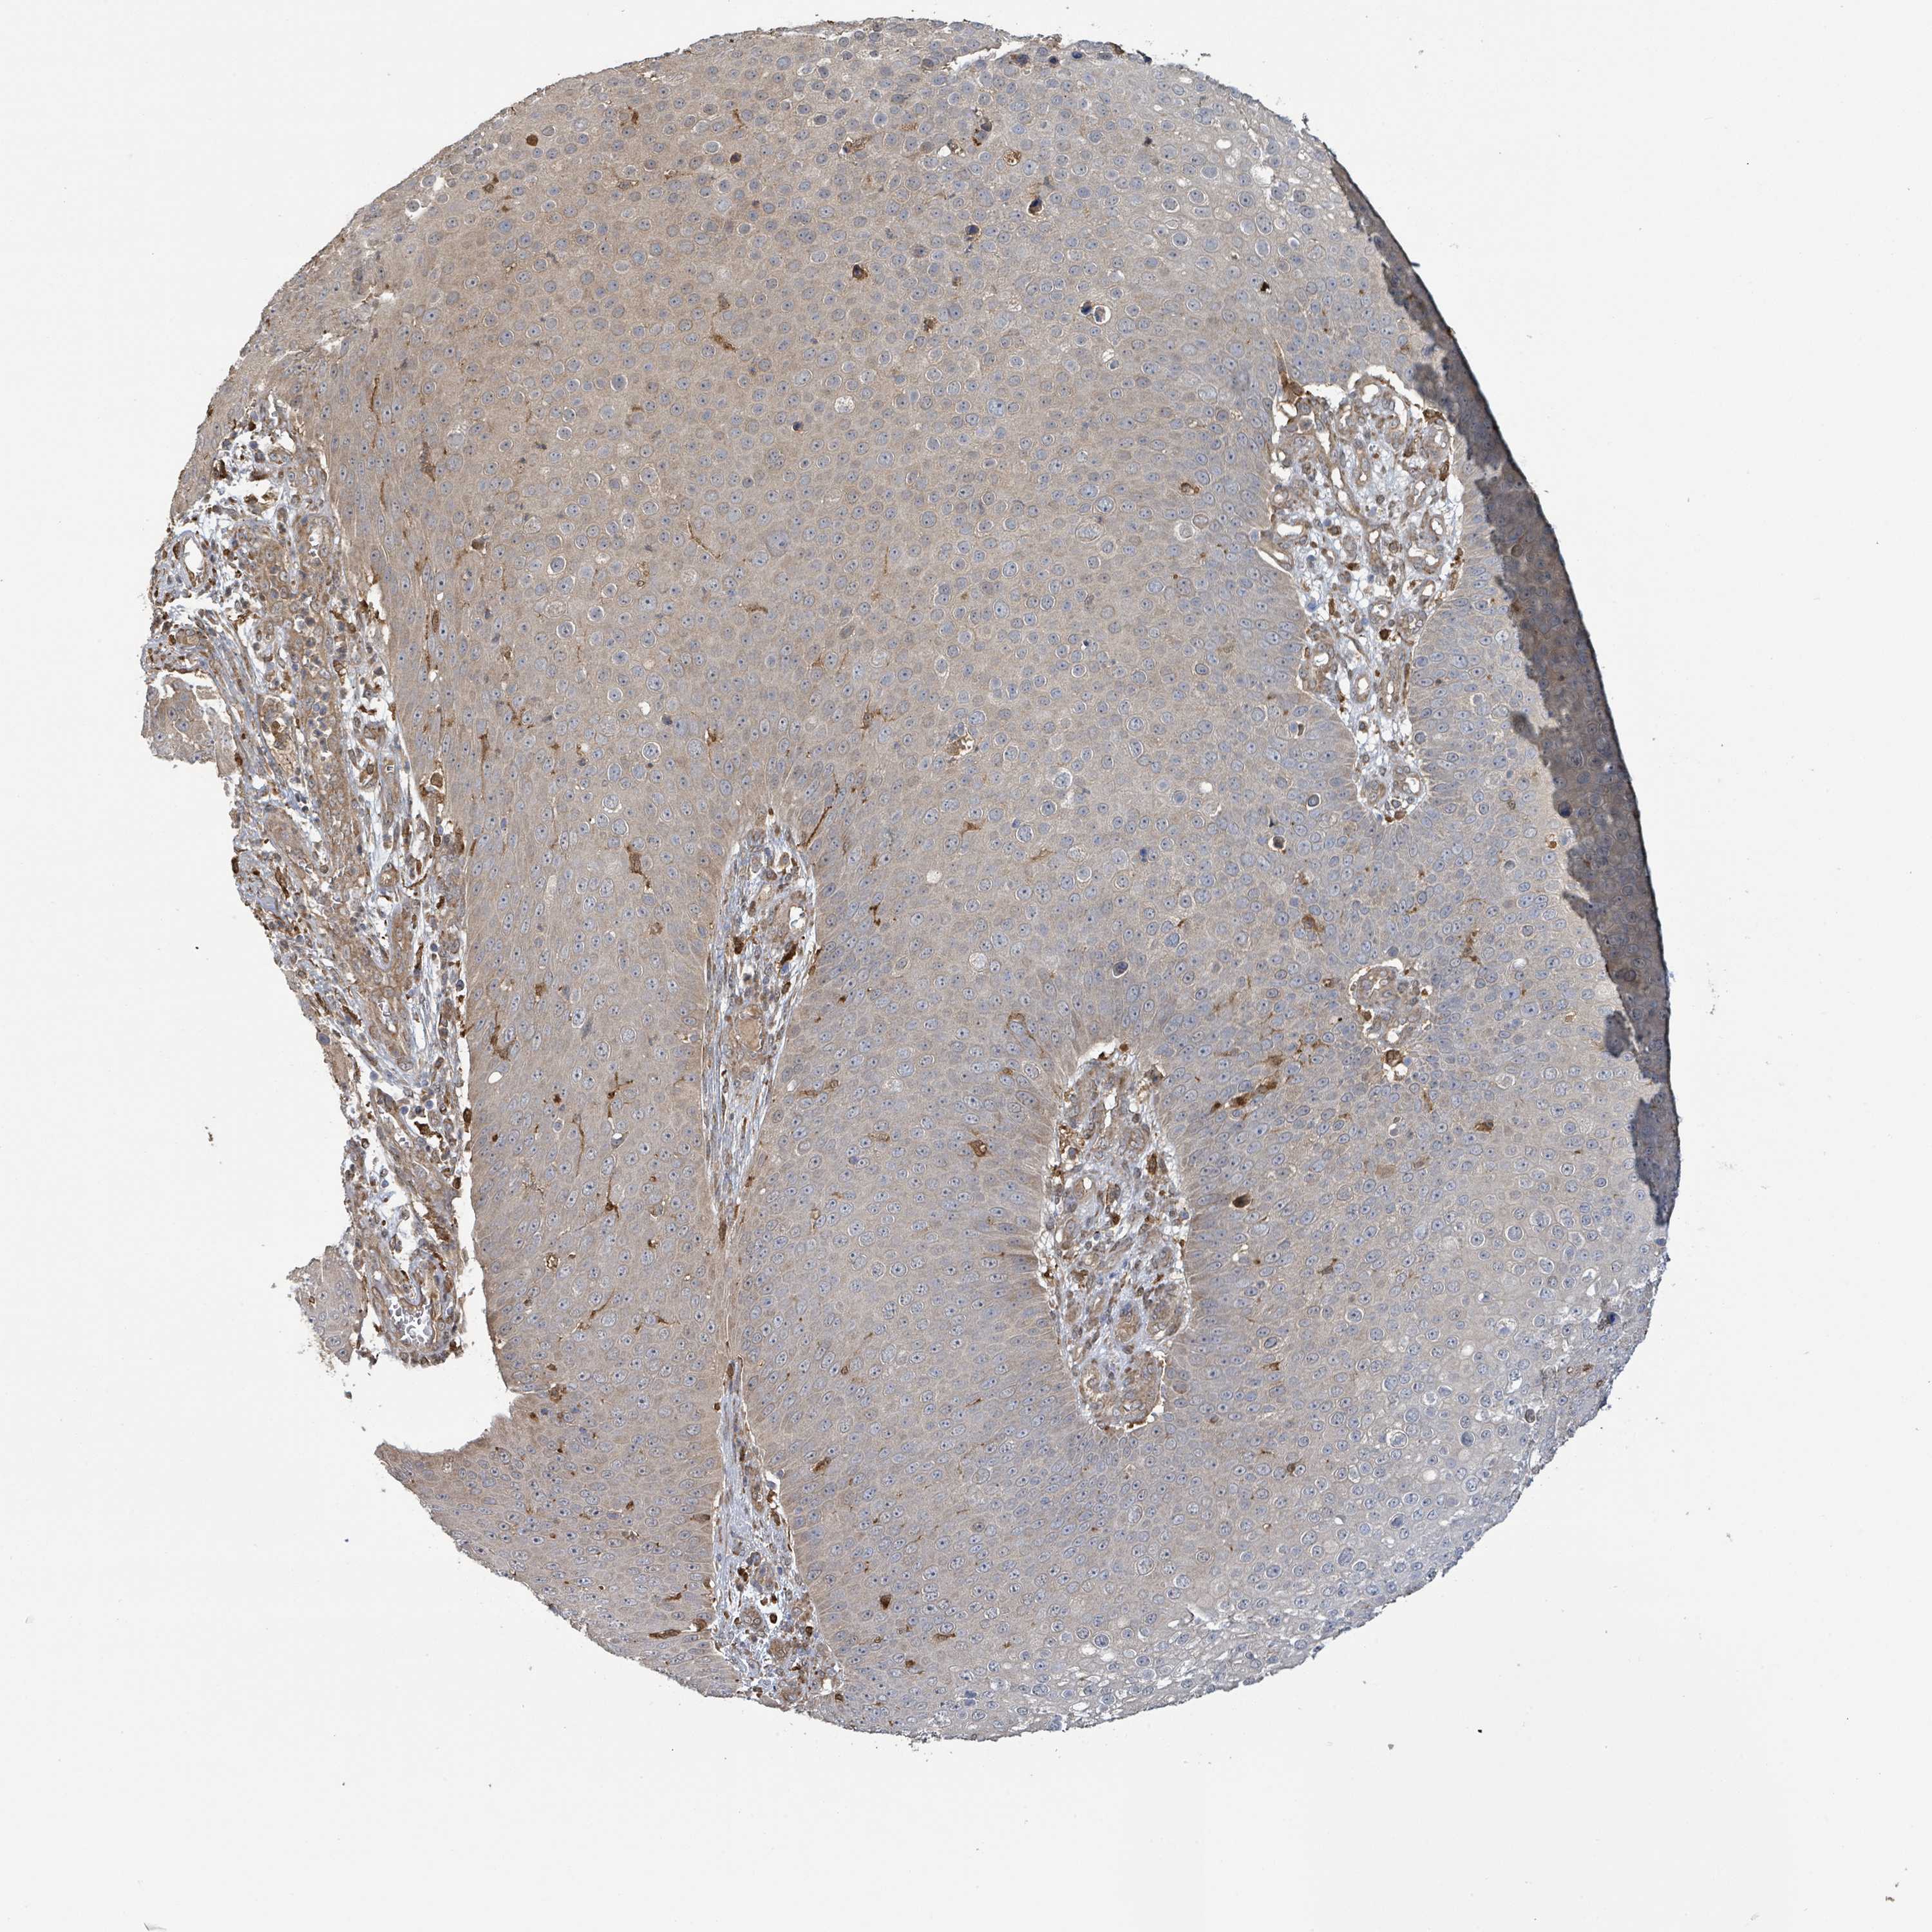

Basal cell and squamous cell cancer

SKIN CANCER - Protein expressioni

A mouse-over function shows sample information and annotation data. Click on an image to view it in a full screen mode. Samples can be filtered based on level of antibody staining by selecting one or several of the following categories: high, medium, low and not detected. The assay and annotation is described here.

Antibody stainingi

Antibody staining in the annotated cell types in the current human tissue is reported as not detected, low, medium, or high, based on conventional immunohistochemistry profiling in selected tissues. This score is based on the combination of the staining intensity and fraction of stained cells.

Each image is clickable and will lead to virtual microscopy that enables deeper exploration of all samples and also displays staining intensity scores, fraction scores and subcellular localization as well as patient and tissue information for each sample.

Basal cell carcinoma